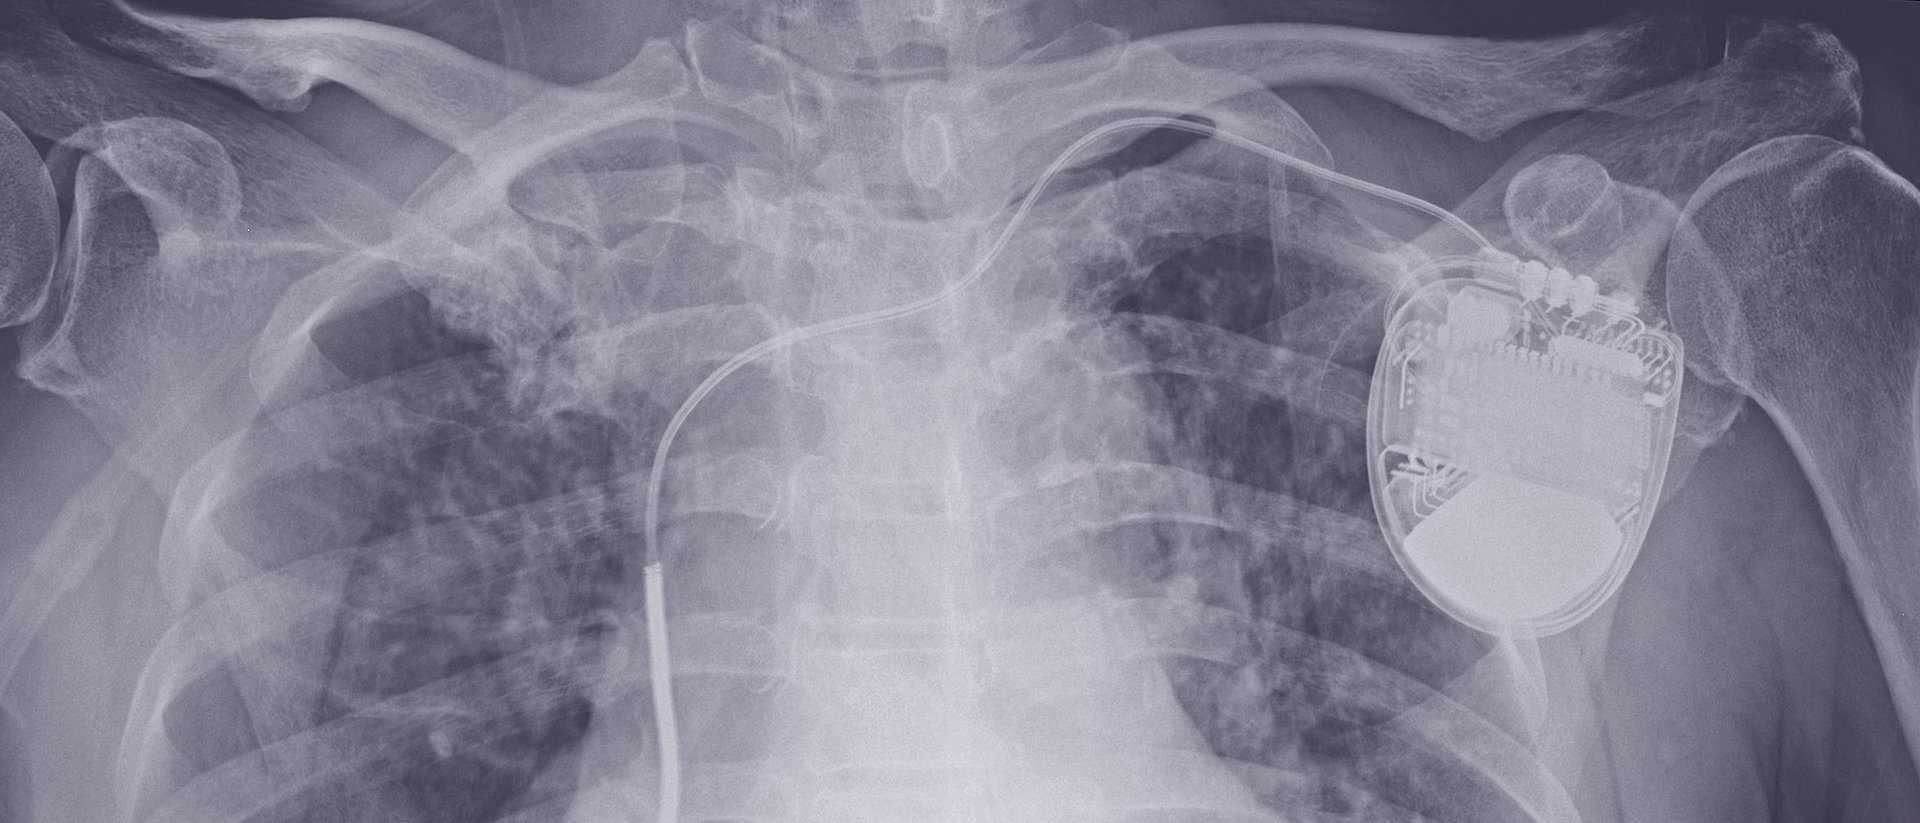

Röntgenbild eines Patienten mit implantiertem Defibrillator. iStock.com / Tonpor Kasa

Bei lebensbedrohlichen Herz-Rhythmus-Störungen kann ein starker elektrischer Impuls den Herzmuskel wieder in den richtigen Takt bringen. Das ist die Aufgabe von Defibrillatoren, die wie Herzschrittmacher in den Brustkorb eingesetzt werden. Ärztliche Leitlinien sehen vor, dass diese Geräte bei bestimmten Herzerkrankungen vorbeugend eingesetzt werden. In der EU geschieht das jährlich mehr als 100.000-mal. Das bedeutet nicht nur hohe Kosten für das Gesundheitssystem, die Geräte stellen auch ein Risiko dar: Schätzungen zufolge kommt es bei jedem vierten eingesetzten Defibrillator innerhalb von zehn Jahren zu erheblichen Komplikationen – von Infektionen bis hin zu spontanen Stromschlägen.